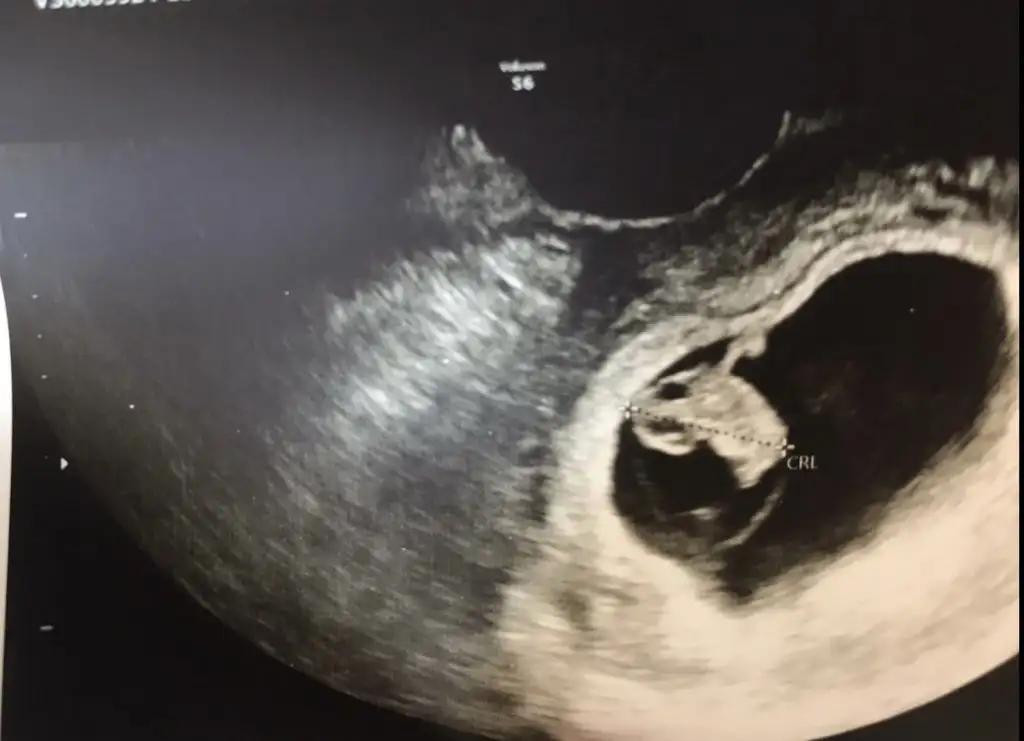

8+4 günlüğüz

Bu arada sağ yumurtalıktan olmus

• 9D930B68-160C-4C42-97C9-44860B585911.webp

14,1 KB · Görüntüleme: 172

• 35AB6AB0-F2DC-4F1B-A1D3-B1A39A8BA81C.webp

25,6 KB · Görüntüleme: 169